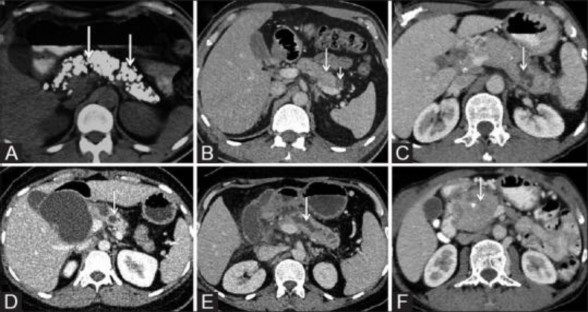

Hình 1.4. Tổn thương tụy trên cắt lớp vi tính

A. Sỏi tụy. B. Tụy teo nhỏ và nang tụy kích thước nhỏ. C - E. Ống tụy chính giãn, thành ống tụy chính không đều. D. Nang giả tụy. F. Sỏi ống tụy trên bệnh

nhân u đầu tụy.

(Nguồn: Kamat R., Indian Journal of Radiology and Imaging, 2019) [72]